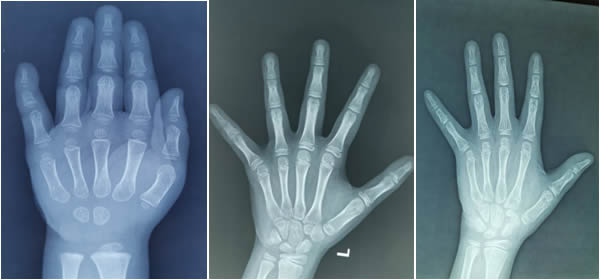

了解人的骨齡的第一步:拍攝人左手手腕部的X光片,如下圖(tú)。

雖然手型各有千(qiān)秋,人類骨骼發育的變化進程卻基本相似,每一根骨頭的發育過程都具有連續性和階段性(xìng)。不同階段的骨頭具有不同的形態特點,手腕部是公認的適宜觀察骨(gǔ)發育和測定骨齡的主要部位,適合於各(gè)年齡組。因此,醫生通過(guò)X光片觀察左手掌(zhǎng)指骨、腕骨(gǔ)及橈尺骨下(xià)端的骨化中心的(de)發育程度,來(lái)確定骨齡。